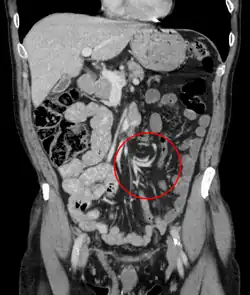

A clínica é típica de abdômen agudo. O diagnóstico normalmente é feito com Raio-X (parece um balão radiolúcido ou com grãos de café) e tomografia computadorizada.